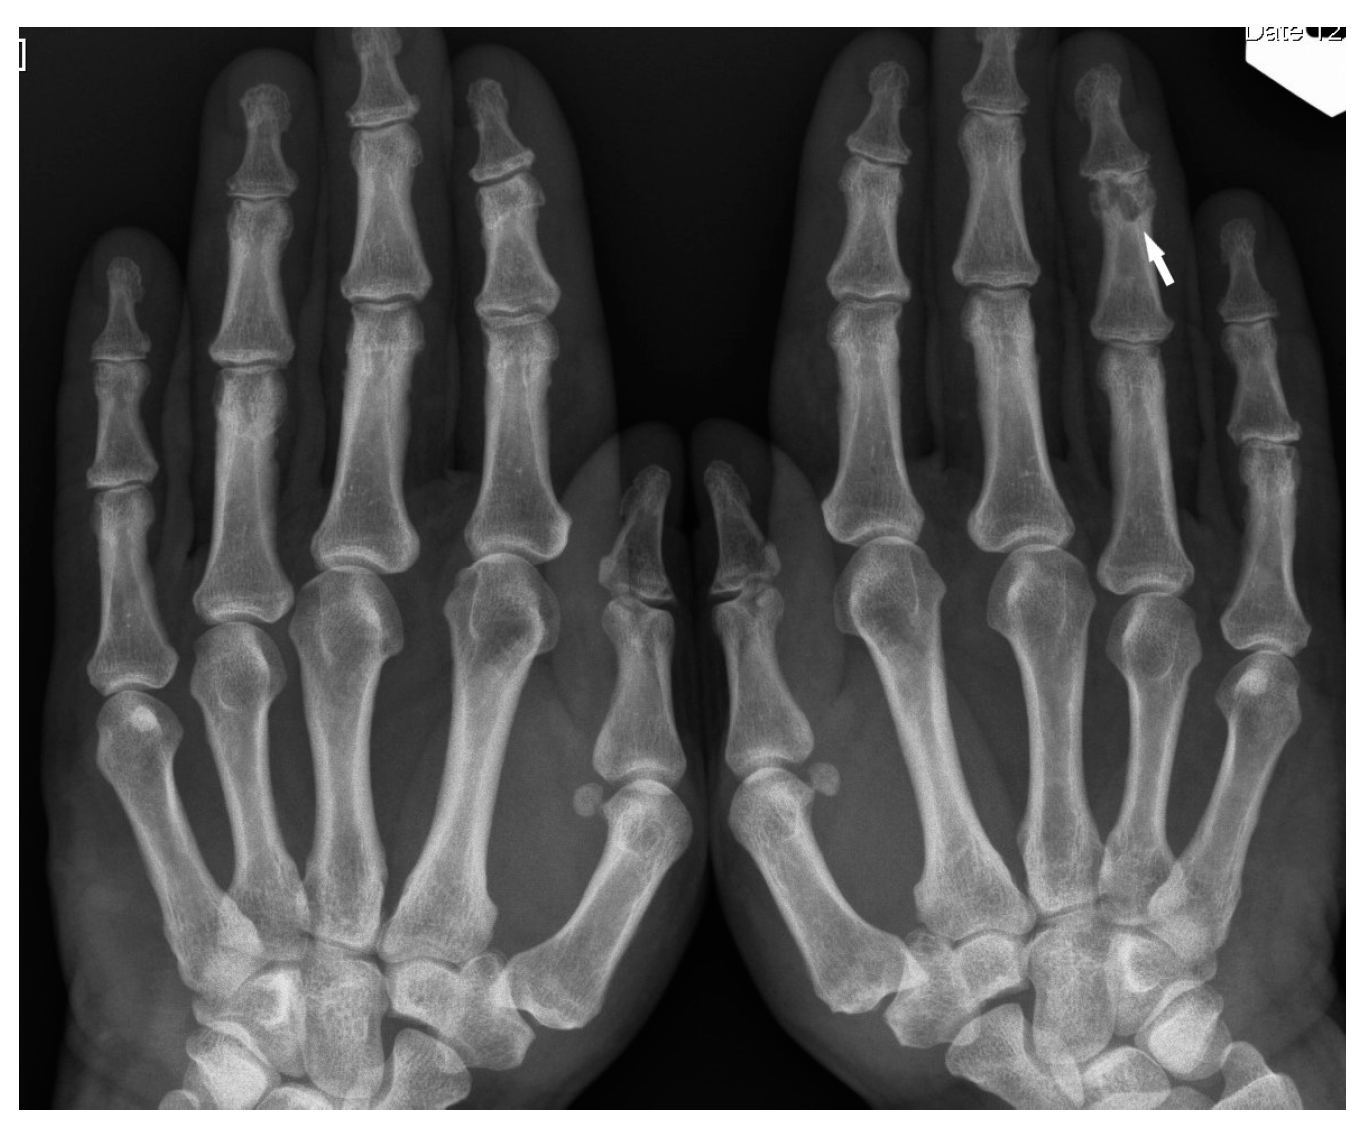

Bone sarcoidosis was first described in 1903 by Kreibich as the image of lace in the phalanges of the hands and this is considered the classic presentation of small bone involvement [8].

The typical cystic X-ray pattern of bone sarcoidosis was described for small bones of the hands only (Figure 1). Other skeletal sites of sarcoidosis evaluated by this modality may be a diagnostic challenge, showing no typical radiologic features of the disease. Increasingly used modern diagnostic methods such as MRI and PET-CT indicate that multifocal bone lesions are sometimes undetectable on X-ray [10,11,12].

Figure 1. X-ray of the finger. Sarcoidosis. Cystic lesions in the middle phalanx head (white arrow).

Figure 7. X-ray of the hands, PA. Unilateral osteolytic-cystic lesions in the subchondral layer of the middle phalanx of the 4th finger of the left hand (white arrow).